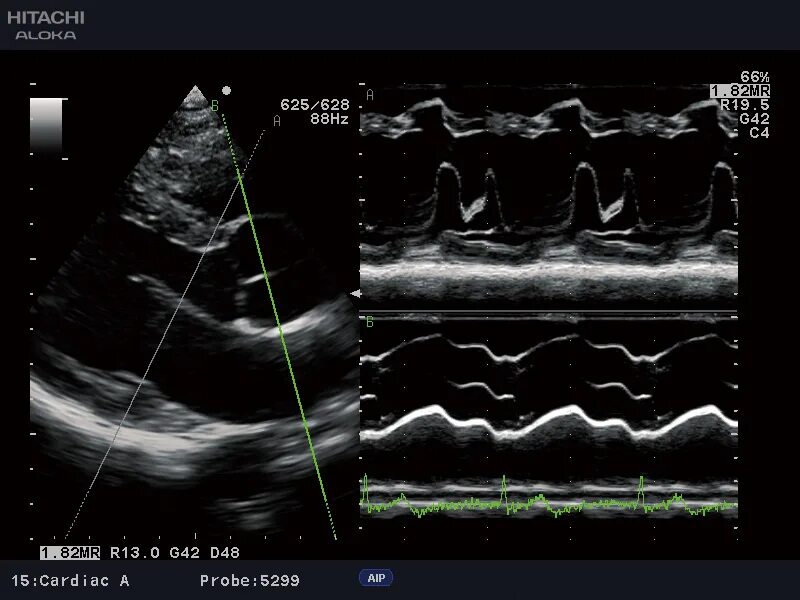

Режимы узи аппарата